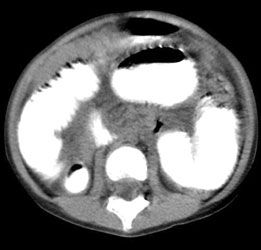

Results of a complete blood cell count and a comprehensive metabolic panel, including amylase and lipase, were normal. An abdominal radiograph showed dilated loops of small bowel with multiple air-fluid levels (Figure 1). Upper GI series with small-bowel follow-through showed dilated small-bowel loops--suggestive of distal small-bowel obstruction. CT scans of the abdomen revealed a distended stomach and significant small-bowel dilatation (Figure 2) with no mass.

Figure 2 - A CT scan of the abdomen shows small-bowel dilatation.